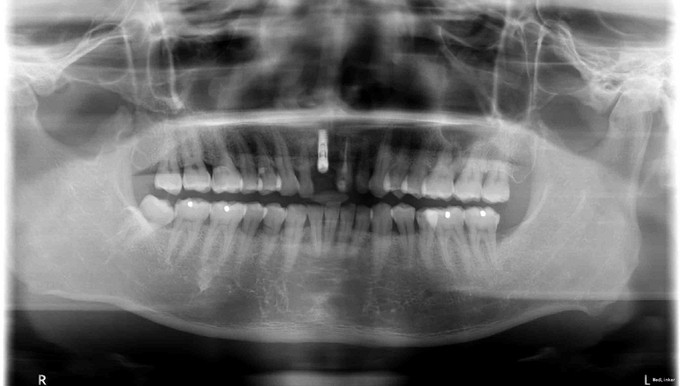

诊断:牙列缺损 复诊拍片骨质可(缺X片),常规消毒铺巾,碧蓝麻局部麻醉,常规牙槽脊切口,逐级备洞,植入XIVE种植体3.4*10mm,接入愈合基台穿龈愈合,约期复诊冲洗。

延期种植指在拔牙3 个月或更久,拔牙创愈合、新生骨充满拔牙窝后将种植体植入健康、丰满的牙槽骨。延期种植避免了拔牙后牙槽骨可能存在的感 染,新骨生成后可提供较充足的骨量从而使种植体易于获得良好的初期稳定性。此种术式是传统的种植方法,也是目前多数种植系统所推荐的最为安全 的种植外科方案